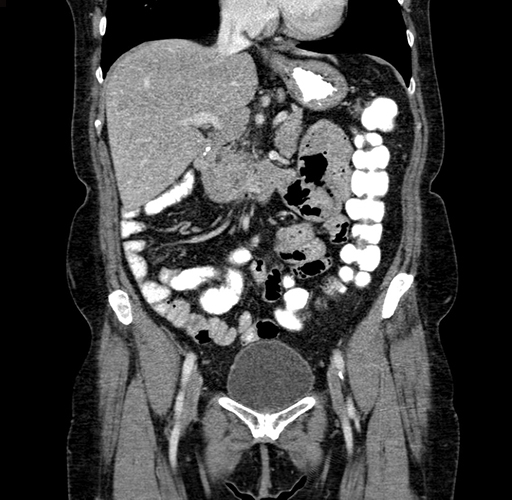

Axial Venous

Coronal Venous